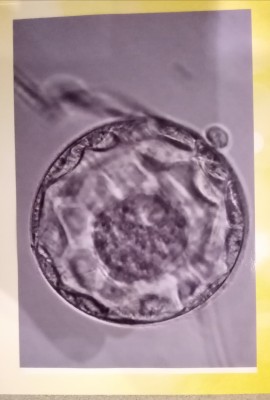

die BC sieht sehr gut aus, ich würde sie mit 4AB einstufen, optimale Voraussetzungen

für den Transfer.